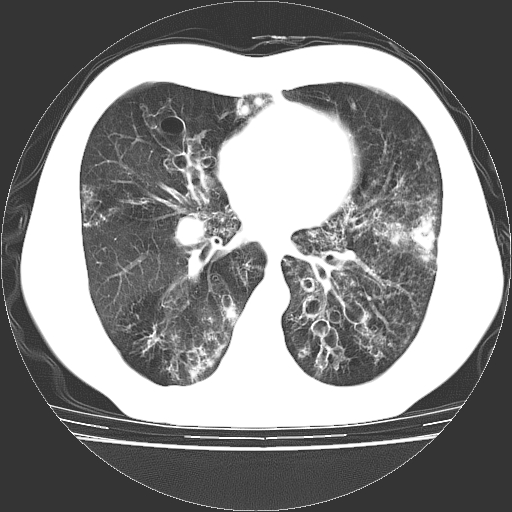

以下是引用zyx168在2006-12-4 15:30:00的发言:[br]经典!支气管肺囊肿并感染。

以下是引用dyqct在2006-12-4 17:11:00的发言:[br]典型的囊状支扩合并感染。

以下是引用liaoqiang在2006-12-4 16:12:00的发言:[br]局部肺叶内可见扩张的支气管壁,考虑为支扩。部份囊样影内有小液平和肺内散布斑片征影、小结节及纤维灶,提示支扩伴感染,且由于局部呈现有树芽征感染以结核可能性大。

以下是引用zhoucan076在2006-12-4 16:48:00的发言:[br]囊状支扩合并感染